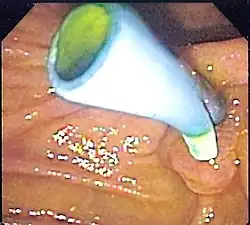

A colon stent is typically made of flexible metal mesh that can expand and hold open the blocked area, allowing for the passage of stool. Colon stents are used primarily as a palliative treatment for patients with advanced colorectal cancer who are not candidates for surgery. They help relieve symptoms such as abdominal pain, constipation, and bowel obstruction caused by tumors or strictures in the colon.

The placement of a colon stent involves endoscopic techniques similar to esophageal stenting. A thin tube called an endoscope is inserted into the rectum and guided through the colon to locate the blockage. Using fluoroscopy or endoscopic guidance, a guidewire is passed through the narrowed area and then removed after positioning it properly. The stent is then delivered over the guidewire and expanded to keep open the obstructed section of the colon. Complications associated with colon stents include perforation of the intestinal wall, migration or dislodgment of the stent, bleeding, infection at insertion site, or tissue overgrowth around it.[10]

Colon stenting provides several benefits including prompt relief from bowel obstruction symptoms without invasive surgery in many cases. It allows for faster recovery time compared to surgical interventions while providing palliative care for patients with advanced colorectal cancer by improving quality of life and enabling better nutritional intake. However, there are potential risks associated with complications such as migration or obstruction that may require additional procedures or interventions to address these issues effectively.[11]